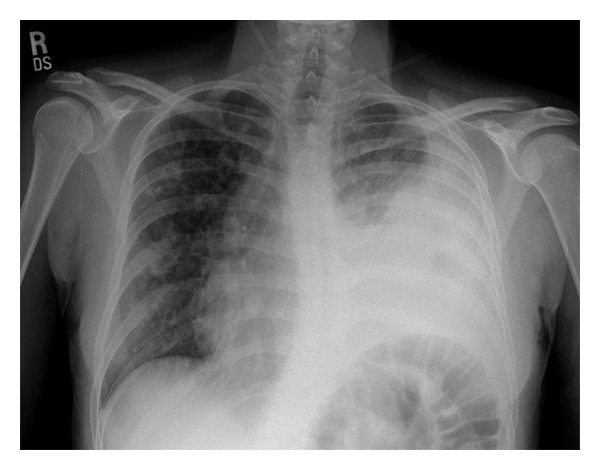

Input 3: What is seen in the X-ray and what should be done? ![]()

Visual input constitutes a vital component of the medical domain, supplying indispensable information in healthcare environments. Healthcare professionals extensively depend on visual cues for diagnosis, monitoring, and treatment of patients. Medical imaging technologies, such as X-rays, CT scans, and MRIs, offer unparalleled insight into internal organs, detecting diseases and abnormalities that may be invisible to the naked eye. Additionally, scientific figures and medical records, including plots, charts, and tables, are prevalent in the medical field. We propose linking visual experts with Med-Alpaca, as foundation model chaining presents a modular and highly adaptable framework for incorporating a diverse array of visual modules. Within this framework, any multimodal task can be divided into two essential stages: (1) the conversion of images to text, and (2) cognitive reasoning based on the derived text. In our context, visual experts (i.e., visual foundation models) transform medical images into an intermediate text representation. This converted data is then used to prompt a pretrained LLM, leveraging the inherent few-shot reasoning capabilities of LLMs to generate appropriate responses. Currently, our platform supports two distinct visual experts: Med-GIT and DePlot, chosen due to the widespread presence of radiology images and plots within the medical domain. The system's architecture is also designed to enable seamless integration of alternative medical visual experts, and we plan to incorporate additional medical visual foundation models as visual experts in the near future. The Med-GIT model represents a GIT: Generative Image-to-text Transformer for Vision and Language, fine-tuned specifically on the ROCO dataset to facilitate specialized radiology image captioning. The training procedure for the model is outlined in comprehensive detail in our publicly accessible Github repository.